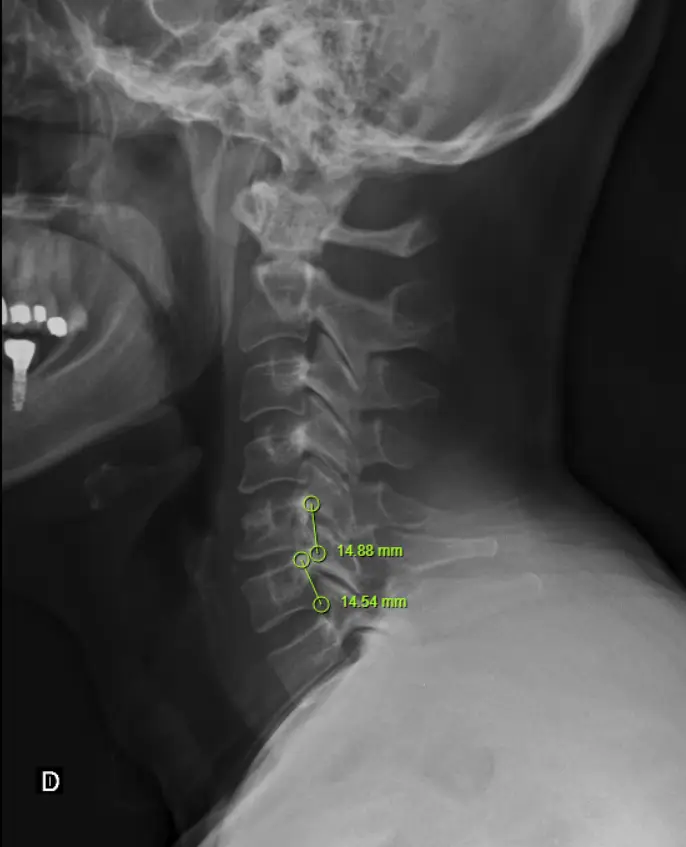

Imágenes

Estudios como radiografías, resonancias, etc., pueden ser necesarios en caso de que el profesional lo considere. Brindan mayor especificidad.

Estudios como radiografías, resonancias, etc., pueden ser necesarios en caso de que el profesional lo considere.